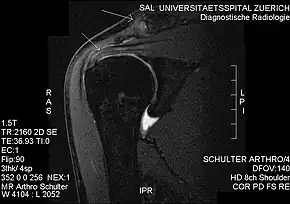

Imaging

Plain x-rays of the shoulder can be used to detect some joint pathology and variations in the bones, including acromioclavicular arthritis, variations in the acromion, and calcification. However, x-rays do not allow visualization of soft tissue and thus hold a low diagnostic value.[2] Ultrasonography, arthrography and MRI can be used to detect rotator cuff muscle pathology. MRI is the best imaging test prior to arthroscopic surgery.[2] Due to lack of understanding of the pathoaetiology, and lack of diagnostic accuracy in the assessment process by many physicians,[19] several opinions are recommended before intervention.